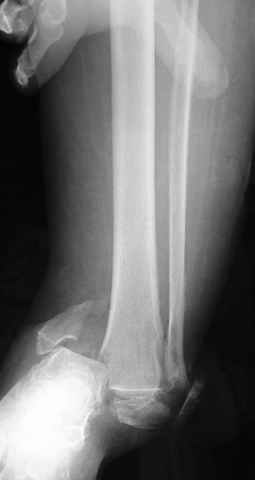

Dear all,40 y.o. man had sustained this terrible fracture falling from a motorbike.

Closed fracture.

This is really Pilon Fx (C3.3; the high energy and the extent of distal tibia comminution are defining it).

After some days of traction I would like to insert an external fixator (I think a circular one instead of a monoaxial one, because of the multiplanar situation of the fracture).